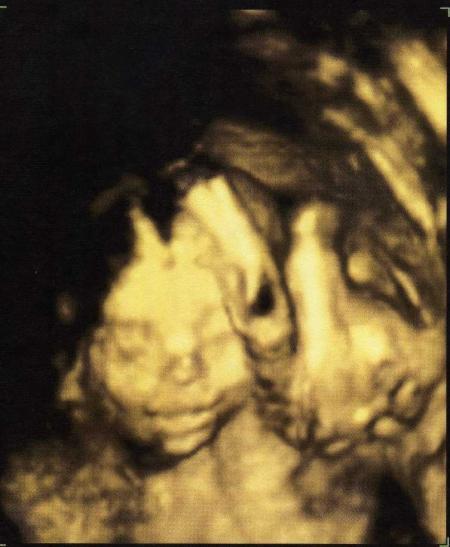

Hallo... wir hatten heute unsere Feindiagnostik und nu ist es sicher, dass wir ein Pärchen bekommen.. Die beiden sind auch soweit zeitgerecht entwickelt..das Mädel ist ein bisschen kleiner als der Junge, aber das darf ja ruhig so sein..:-) Was er aber festgestellt hat, ist, dass das Mädchen ein bisschen wenig Fruchtwasser hat. Liegt so im unteren Normbereich. Das muss dann öfter kontrolliert werden. Ich hoffe, da bleibt alles in Ordnung, weil beim Fruchtwasser kann man ja echt so gar nichts machen... Ich freu mich erstmal, dass beide gesund und munter sind...:-)) Das 1. Bild ist der Junge... LG, Caro

Bild zu Brüderchen und Schwesterchen :-)) - Forum für September - Mamis

na dann nochmal herzlichen glückwunsch zum pärchen das mädel sieht auf dem bild aus als würde es lächeln

Vielen lieben Dank..:-)) Ja, wir freuen uns auch riesig... ...und das Bild von dem Mädchen ist einfach nur zum verlieben... Und wegen dem Fruchtwasser...da bin ich doch etwas beruhigter jetzt, wenn man da zur Not doch was machen könnte...Es ist ja auch alles noch im Normbereich, halt nur untere Grenze..